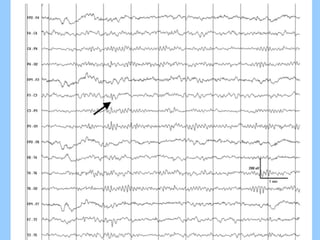

1. The document discusses EEG patterns and findings in various neurological conditions seen in children. It includes descriptions of normal EEG findings as well as abnormal patterns seen in conditions like absence seizures, West syndrome, benign childhood epilepsy with centrotemporal spikes, Lennox-Gastaut syndrome, non-convulsive status epilepticus, subacute sclerosing panencephalitis, and herpes encephalitis.

2. Case studies are presented with clinical histories and EEG findings to illustrate different pathologies. Treatment options are also mentioned for many of the conditions.